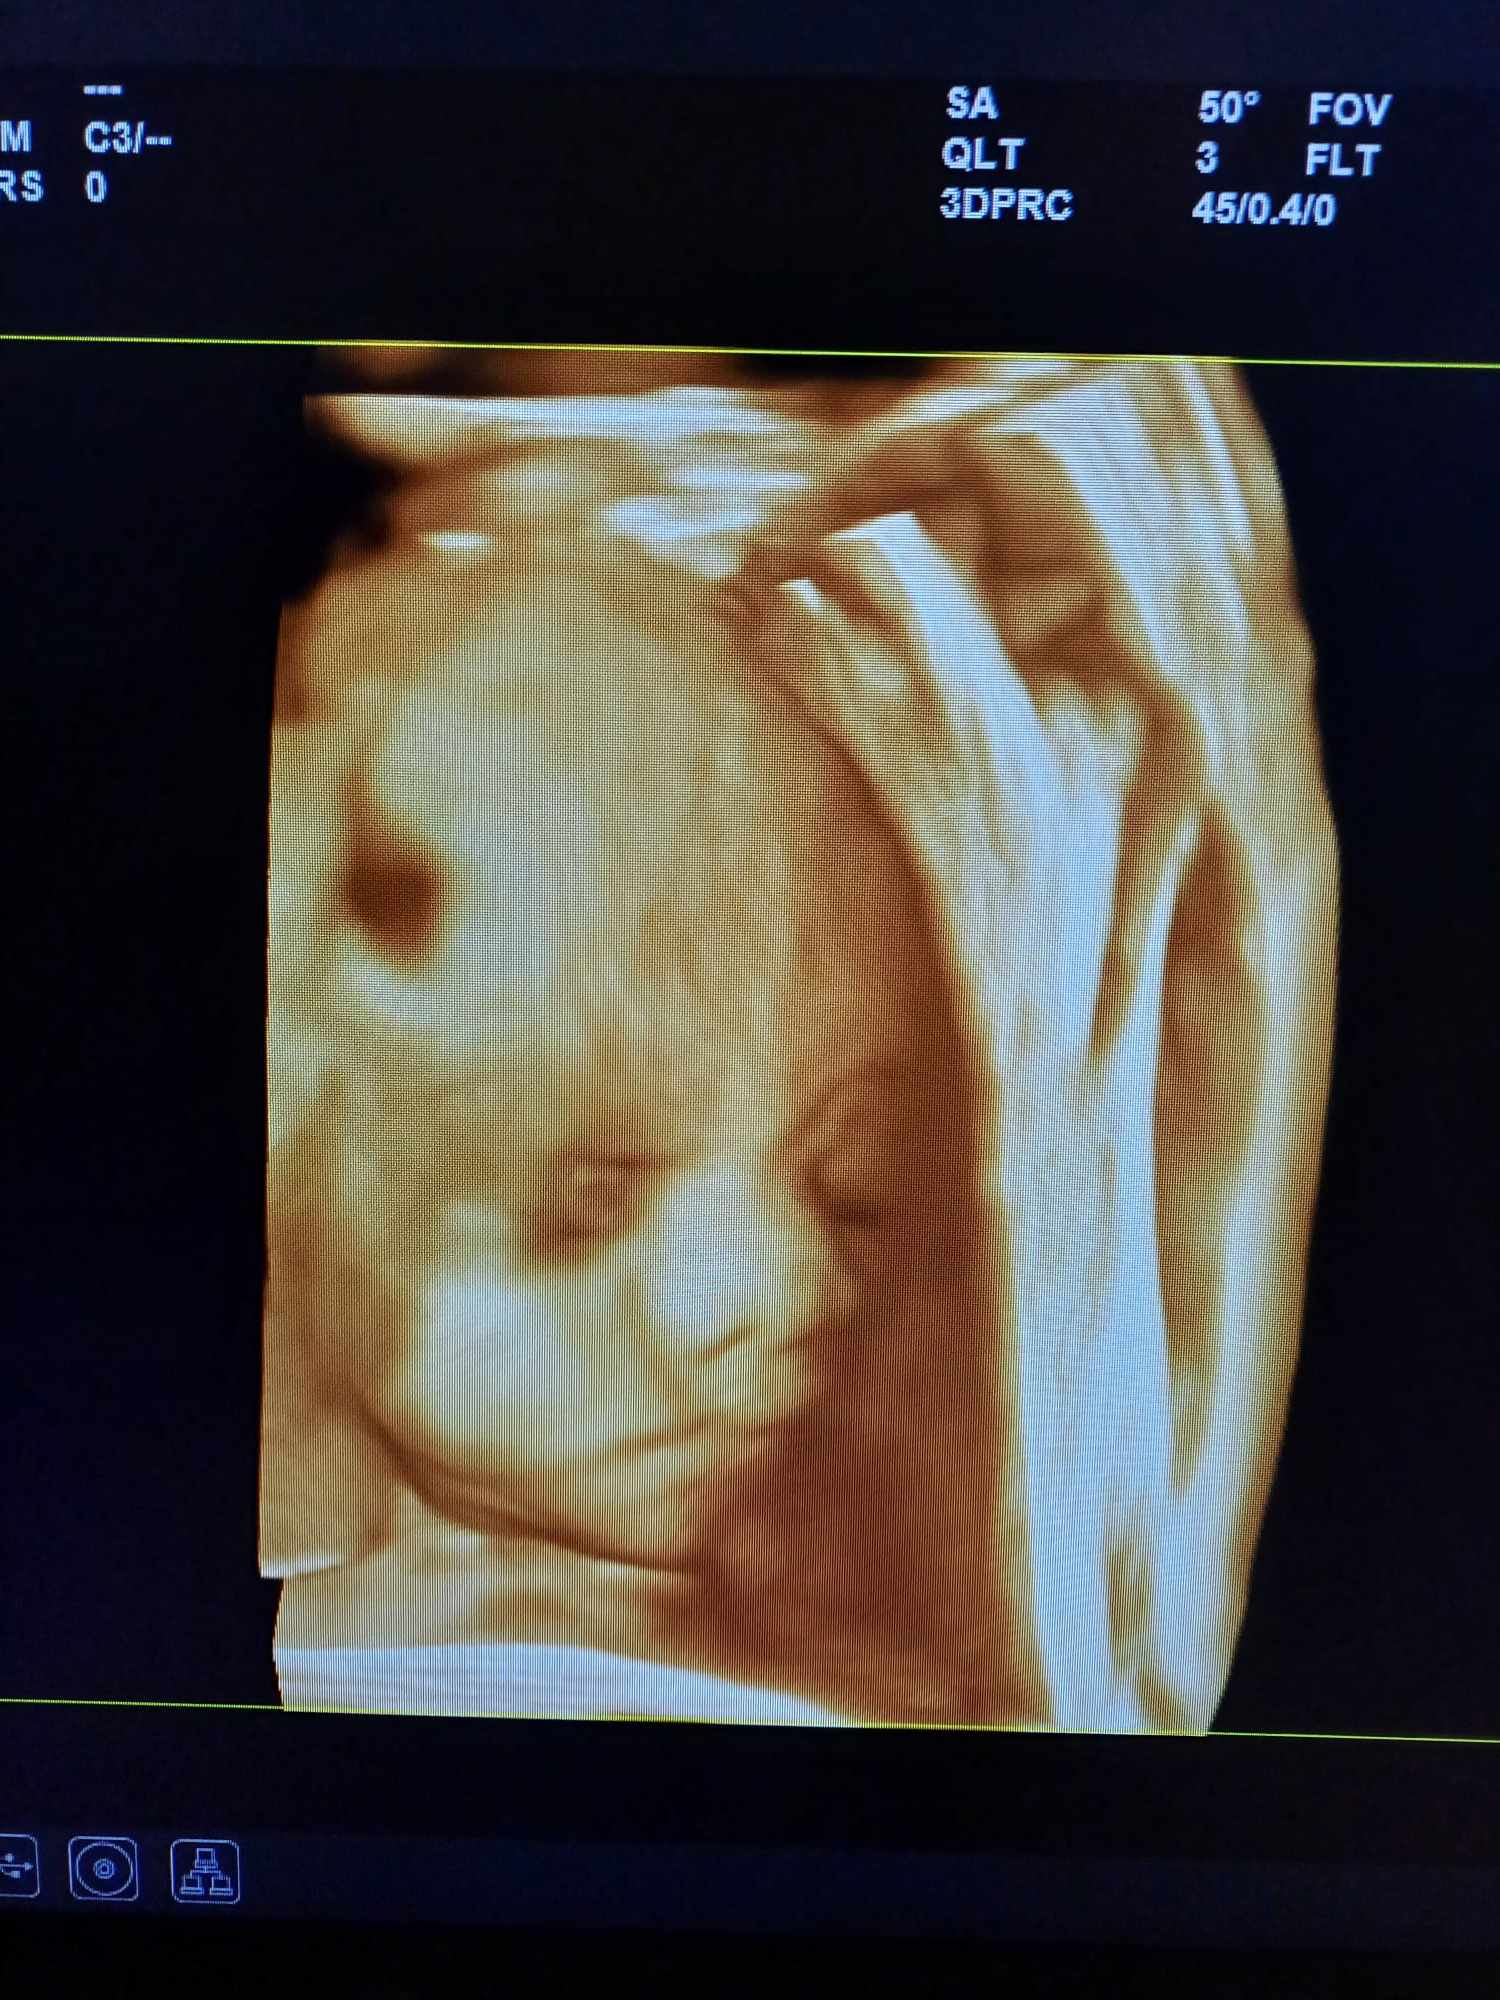

Pozrite si fotky z nášho moderného pracovného prostredia

Naša gynekologická ambulancia je vybavená modernou technikou a poskytuje pacientkom príjemné a komfortné prostredie pre všetky druhy vyšetrení a konzultácií.